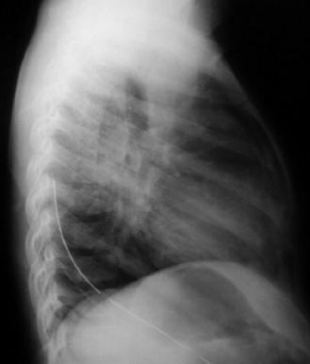

Radiología del tórax

• Rx. tórax PA: Observamos lesiones quísticas múltiples en base pulmonar derecho, aumento del volumen pulmonar a predominio basal derecho con mayor transparencia y discreta desviación contra lateral del mediastino.

• Rx. tórax lateral: Se aprecia mayor transparencia pulmonar y lesiones quísticas múltiples en todos los segmentos correspondientes al lóbulo pulmonar inferior derecho.

• No se observan lesiones de atelectasia, nódulos pulmonares ni adenopatias del mediastino